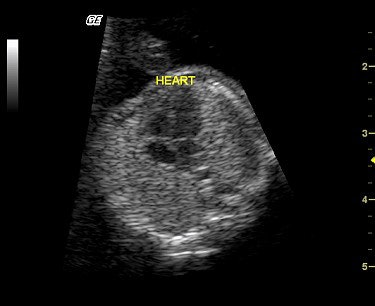

![]() |

| The fetal cardiac scan depicts the heart at 14 weeks’ gestation (8 mm). More than half of fetal cardiac anomalies can be spotted in an early scan, using high-resolution transvaginal ultrasonography. Image courtesy of Dr. Reuben Achiron. |